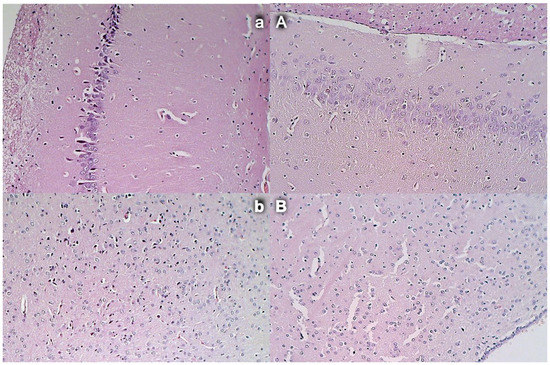

Figure 10. Stomach and duodenal injury (HE x100). Control rats show marked transmural congestion within the lamina propria of the stomach (a, left, upper) and duodenum (b, left, low). Blunt duodenal villi and mild hyperplasia of the crypts. Contrarily, BPC 157 rats exhibit only mild congestion, with preserved stomach (A, right, upper) and duodenal (B, right, low) architecture of the mucosa.

Figure 11. Intestinal injury (HE, ×100 (upper), ×200 (low)). Controls presented with moderately severe mucosal injury with a reduction of intestinal villi; more severe mucosal injury with lumen dilatation of the colon and a reduction of crypts (a,b, left). Contrarily, BPC 157-treated rats exhibited only mild congestion, with preserved mucosal intestinal architecture (A,B, right).

3.9. Stomach, Duodenum, and Intestinal Injury

Without therapy, all of the rats with an occluded superior mesenteric artery exhibited marked transmural congestion within the stomach, duodenum, and small and large bowel wall, with an ascending sequence from the stomach to the large bowel (Figure 10 and Figure 11). Illustratively, the stomach dilated capillaries in the lamina propria. Within the small and large bowel mucosa, focal hemorrhage appeared in the lamina propria. Mild mucosal injury appeared with blunt duodenal villi and mild hyperplasia of the crypts while more severe mucosal injury with a reduction of intestinal villi and even more severe mucosal injury with lumen dilatation of the colon and reduction of crypts were observed. Contrarily, in rats with an occluded superior mesenteric artery that received BPC 157 therapy, most of these changes were not found. Only mild congestion was observed.

3.10. Heart Damage

Severe congestion within the myocardium was observed in controls with an occluded superior mesenteric artery while no changes within the myocardium were found in BPC 157-treated rats (Figure 12).

3.11. Lung Damage

Occlusion of the superior mesenteric artery commonly produced focal thickening of the alveolar membranes, lung congestion, pulmonary edema, intra-alveolar hemorrhage, and focal interstitial neutrophil infiltration in controls. Contrarily, BPC 157 rats presented only discrete lung congestion, with no other changes in lung parenchyma (Figure 12).

3.12. Liver Damage

Mild activation of Kupffer cells and severe enlargement of sinusoids with liver congestion appeared in controls with occlusion of the superior mesenteric artery (Figure 13). Contrarily, no changes appeared in liver parenchyma in BPC 157-treated rats.

3.13. Renal Damage

Occlusion of the superior mesenteric artery produced a mild degeneration of proximal tubules, severe vascular congestion, and mild interstitial edema (Figure 13). Contrarily, no changes were found in renal parenchyma in BPC 157-treated rats.